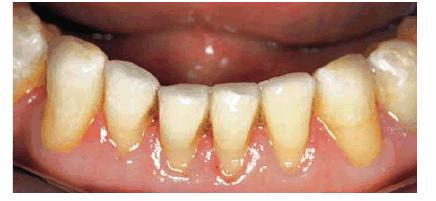

Fixed and removable prosthodontics can be used

to improve appearance and function. The 78-year-old patient in Figures 29-11A and B showed severe wear on his upper and

lower incisors, which compromised his smile line. He also had multiple missing

teeth. He was president of a large company and felt that he looked older than

his actual years because his smile did not show any teeth. His treatment plan

included crowns on his remaining natural teeth and a maxillary precision

attachment removable bridge. The final result shows both improved appearance

and function (Figure 29-11C).

Figure 29-11A and B: This 78-year-old man had worn down his maxillary and mandibular teeth during the course of his life. This negatively affected his smile line.

Figure 29-11C: All of the maxillary and mandibular teeth were crowned and a precision attachment partial denture was made to improve both function and esthetics.